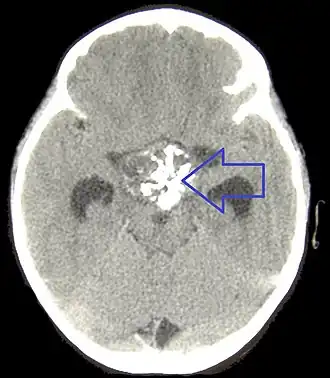

Компьютерная томография

Компьютерная томография головного мозга хорошо выявляет как плотную, так и кистозную части краниофарингиом. Кальцификаты определяются в 95 % случаев у детей и примерно в 50 % у взрослых. Кистозный компонент имеет несколько бо́льшую плотность по сравнению с ликвором, распространяется кпереди и/или латерально и обычно окружает солидный компонент. При введении контрастных веществ яркость узловой части опухоли в половине наблюдений увеличивается на 8—10 единиц Хаунсфилда[32], что встречается в 90 % случаев[33]. Может визуализироваться смещение А1 сегмента передней мозговой артерии или хиазмы зрительного нерва[34].